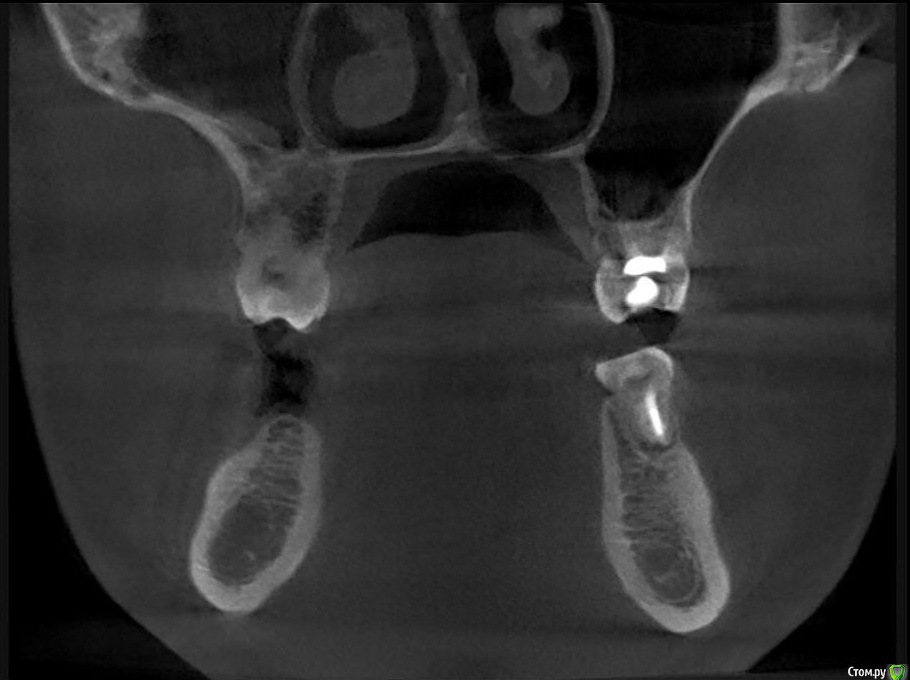

Hans85 Опубликовано 14 января, 2015 Автор Поделиться Опубликовано 14 января, 2015 Полагаю на КТ будет не такая уж радужная картинка...Чем завершено лечение? Коронка?Наконец то пациент пришел на коронку.Вот и Кт ,да заживление не 100% ,но все же . 3 Ссылка на комментарий

Л Ю С Я Опубликовано 10 января, 2014 Поделиться Опубликовано 10 января, 2014 .Новый кейс-совсем свежий пока без долгосрочного результата.Пациентка попала случайно удаляла зуб 28 и хирург сделал ОПТГ,где стали видны обширные периапикальные процессы в области 37 47.Побывав у меня на консультации и услышав план лечения и стоимость,пациентка решила видимо полечить подешевле.,побывав на консультациях в нескольких клиниках и в итоге даже попала к главному стоматологу нашей области. Все ей сказали что удаление онли. Вернулась,-засада была в том что план я писал исходя из ОТПГ не сделав прицел(виноват),сделав прицел понимаю что все сложнее чем я думал-ну что же тем интереснее.Переписав план лечения и подняв ценник на 40%(пациентке не оставалась выбора),начали лечение.1-посещение-ревизия пломбы.понимаю что кто то до меня с маниакальным упорством пытался запломбировать мезиальный язычный канал каналонаполнителями. Убрал два фрагмента из верхней трети мезиального язычного.2-посещение еще фрагмент из мез язычного плюс немного с дистальными поработал(их оказалось два сплит в верхней трети)3-визит обошел фрагмент в мезиальном щечном и доработал остальные каналы.4-визит -паковка.На предпоследнем снимке видны поры-допаковал(просто на финальном не очень видно)Класс! Ждем рекол через 6 месяцев. Паковка чем? Сквирт? Ссылка на комментарий